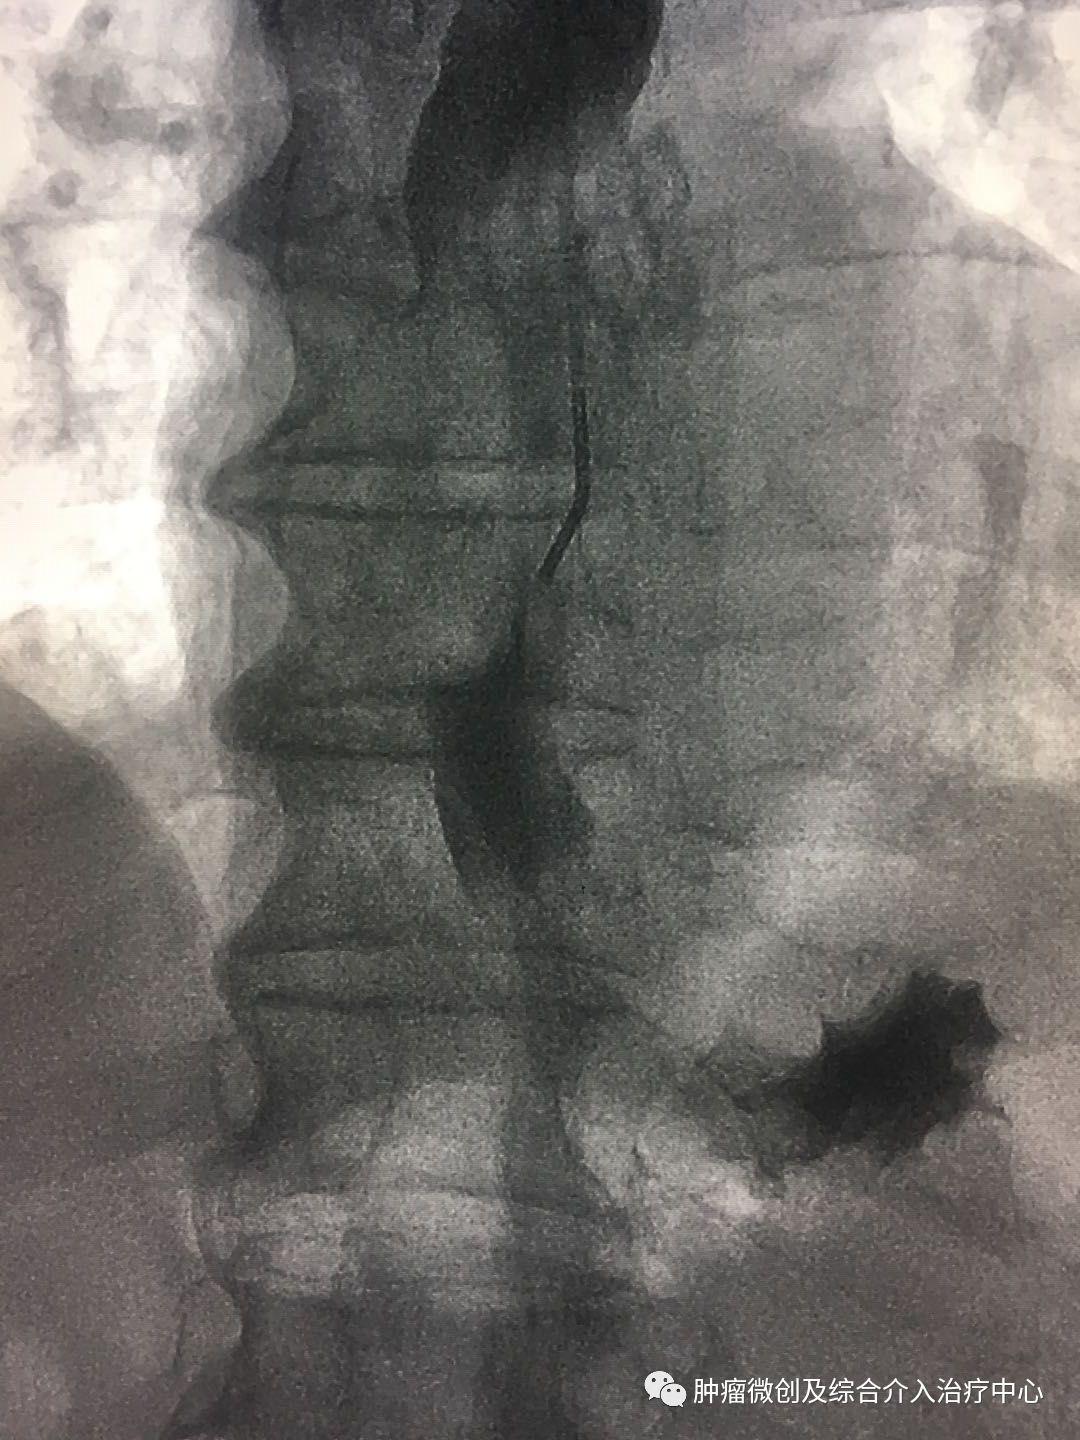

术前造影:食管下段明显狭窄。

在透视下放入食道支架